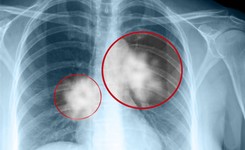

Lekarze oglądają prześwietlenia

Lekarze oglądają prześwietlenia/Shutterstock

Leczenie systemowe jest najczęściej stosowaną metodą w zmaganiach z nowotworami, oprócz chirurgii i radioterapii. Polega na wykorzystaniu leków w ramach tzw. chemioterapii oraz terapii hormonalnej i biologicznej. Najczęstsze leczone nimi nowotwory to rak płuca, na który przypada na świcie 16,4 proc. zachorowań, rak piersi (12,7 proc.) oraz rak jelita grubego (11,1).